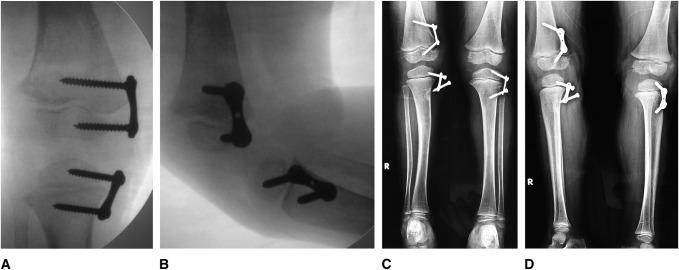

Fifty children (male:female, 27:23) with knee coronal plane deformities (knees:physes, 86:99), (varum:valgum, 51:35) secondary to nutritional rickets were subjected to femoral and/or tibial temporary hemiepiphysiodesis using a two-hole 8-plate. The mean age at implantation was 3.8 ± 1.5 years (range 2.5 to 5). The mean follow-up was 2.8 years (range 2 to 4). All children received a standing full-length AP radiographs of both lower limbs in neutral rotation to measure the mechanical axis deviation, tibiofemoral angle, and joint orientation angles. Tibial torsion was objectively assessed by measuring the bimalleolar axis.

50 例(男/女:27/23)膝关节冠状面畸形(膝/骨骺:86/99)(膝内翻/外翻:51/35)的儿童因营养性佝偻病行股骨和/或胫骨临时半骺阻滞术,采用 2 孔 8 板。植入时的平均年龄为 3.8 ± 1.5 岁(范围 2.5 至 5 岁)。平均随访时间为 2.8 年(范围 2 至 4 年)。所有儿童均接受中立位旋转站立位双下肢全长前后位 X 线片,以测量机械轴偏差、胫股角和关节对线角度。胫骨扭转通过测量双踝轴进行客观评估。